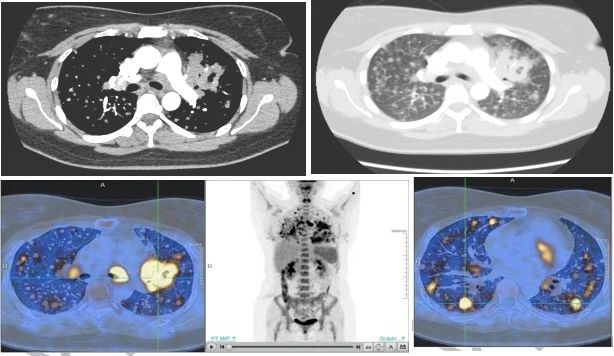

患者为一名双肺多发占位的年轻女性患者,曾在当地医院就诊20余天未能明确诊断,转诊于吉大三院肺癌多学科团队胸外科二病区寻求治疗方案。经过肺癌多学科会诊和详细的入院检查,考虑为恶性肿瘤,首先行肺穿刺活检明确诊断。但异常的是,穿刺组织呈现炎性改变,显微镜下满是脓细胞。当临床诊断和病理初步诊断不符时,就是考验病理医生诊断水平和责任担当的时刻。

经过查阅大量文献,吉大三院病理科做出了ALK阳性间变性大细胞淋巴瘤(ALK+ALCL)伴中性粒细胞增多的最终诊断。因为此病例形态非常罕见,为确保诊断的正确性,病理科又协助家属得到了北京该领域专家周小鸽教授对ALK阳性间变性大细胞淋巴瘤诊断的认可。至此,终于找到了治疗方向,患者及家属重燃了希望,积极投入治疗中。